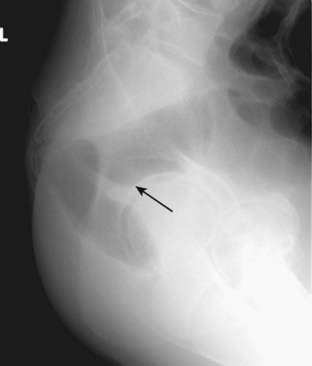

Figure 13-13 Normal lateral view of the rectum.

Frequently, patients are unable to lie prone because of their physical condition (e.g., recent surgery, severe abdominal pain). These patients can turn on their left side and have a lateral view of the rectum exposed with a vertical beam to substitute for the prone radiograph. The lateral view of the rectum will usually demonstrate the presence or absence of air in the rectum and sigmoid (solid black arrow).